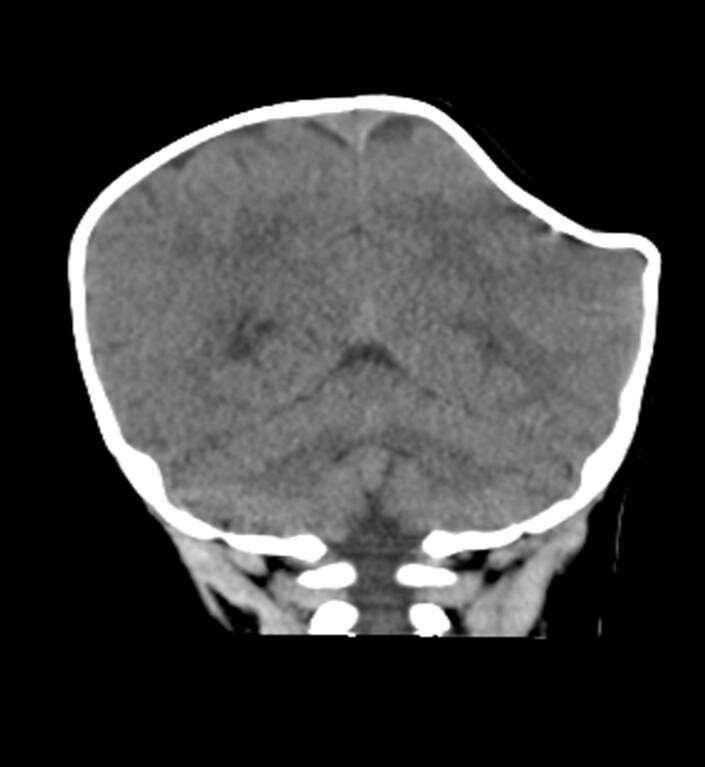

▼寶寶被送到醫院時,左側頭骨凹陷變形,右側頭顱凸起血腫,頭骨凹陷約5X5公分,血腫約5X7公分。幸好寶寶沒有顱內出血,這才保住一命。斷層檢查時,寶寶頭部的影像就像「咬了一口的蘋果」,非常嚇人。